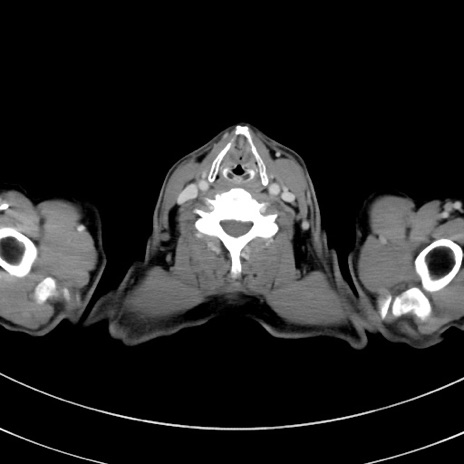

症例8(横断像)

【症例】 60歳代男性

【主訴】 黒色吐物

【現病歴】 4日前から嘔気自覚、2日前の朝食後にも嘔気あり、自分で手で嘔吐反射起こし嘔吐したところ血が混ざっていたため受診。

【既往歴】 5年前汎発性腹膜炎を伴う急性虫垂炎で手術、高血圧、前立腺肥大症、高脂血症

【身体所見】 腹部正中に手術癩痕あり 腹部平坦・軟圧痛なし膨満感あり

【データ】WBC 8400、CRP 4.54